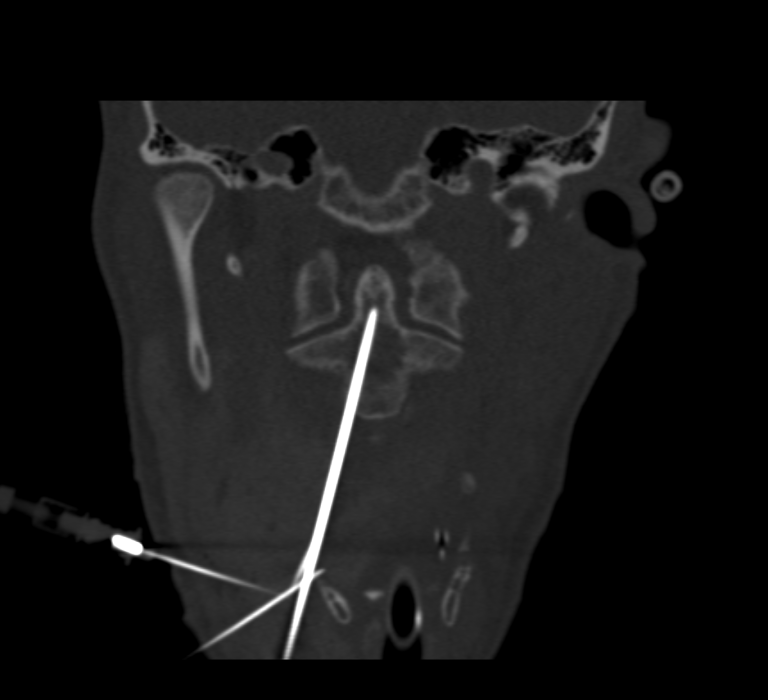

L’intervention se déroule en salle de radiologie interventionnelle, sous anesthésie générale. Grâce à un guidage scanner et scopique en continu, une précision millimétrique est assurée à chaque étape :

• Hydrodissection cervicale : injection de sérum physiologique pour écarter les structures à risque (artère carotide, veine jugulaire, trachée).

• Mise en place de la vis : introduction d’un trocart osseux, puis d’une broche et enfin d’une vis canulée adaptée à l’anatomie du patient.

• Cimentoplastie complémentaire : injection de ciment acrylique dans la lésion pour renforcer la consolidation et la stabilité de la vis.

Cette technique, encore peu répandue en France, est désormais disponible au CHU de Clermont-Ferrand. L’intervention a été réalisée par les Dr Nicolas DE ABREU et Achraf KANAN, sur un plateau technique de pointe.